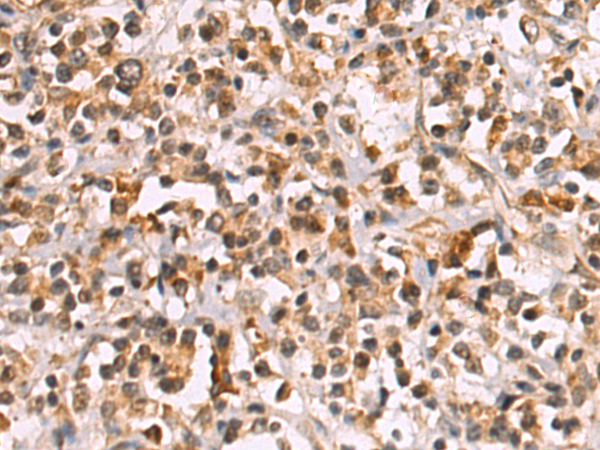

分类: 科研抗体货号: P06463别名: EHB21应用: IHC反应种属: Human, Rat